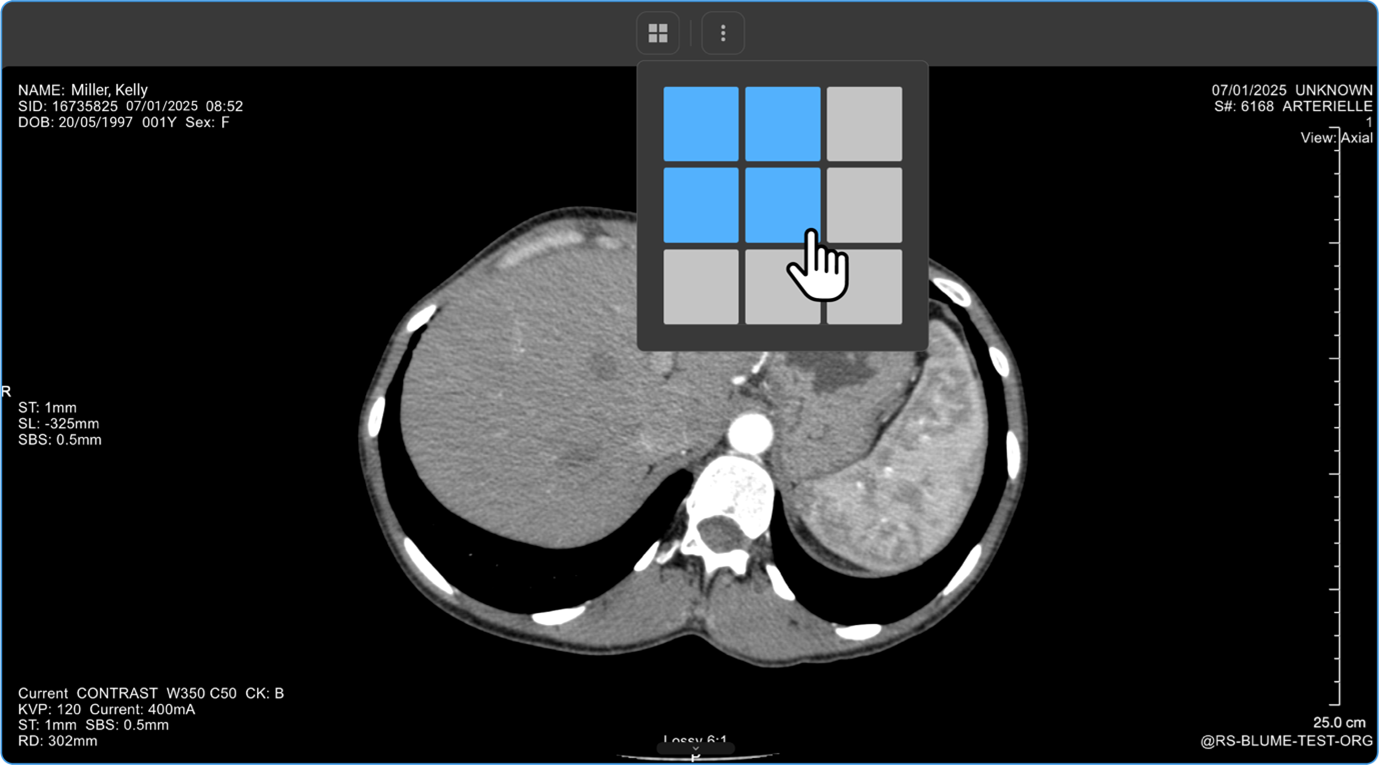

How Do I Change the Viewport Layout?

1. Open Layout Selector from the toolbar.

a. A 3×3 grid appears, with the current layout highlighted.

vai

1. Adjust Viewports:

a. Drag to increase/decrease viewports (up to 8×8 grid per monitor).

How Do I View Multiple Images or Series in Different Layouts?

• If there are multiple images or a series of images, you can customise the display layout to enhance your viewing experience.

• Locate and click on the Change Layout icon in the image viewer toolbar at the top of the screen.

• Select the desired layout format to switch between a single-frame view and a multi-frame display for comparing multiple images simultaneously.